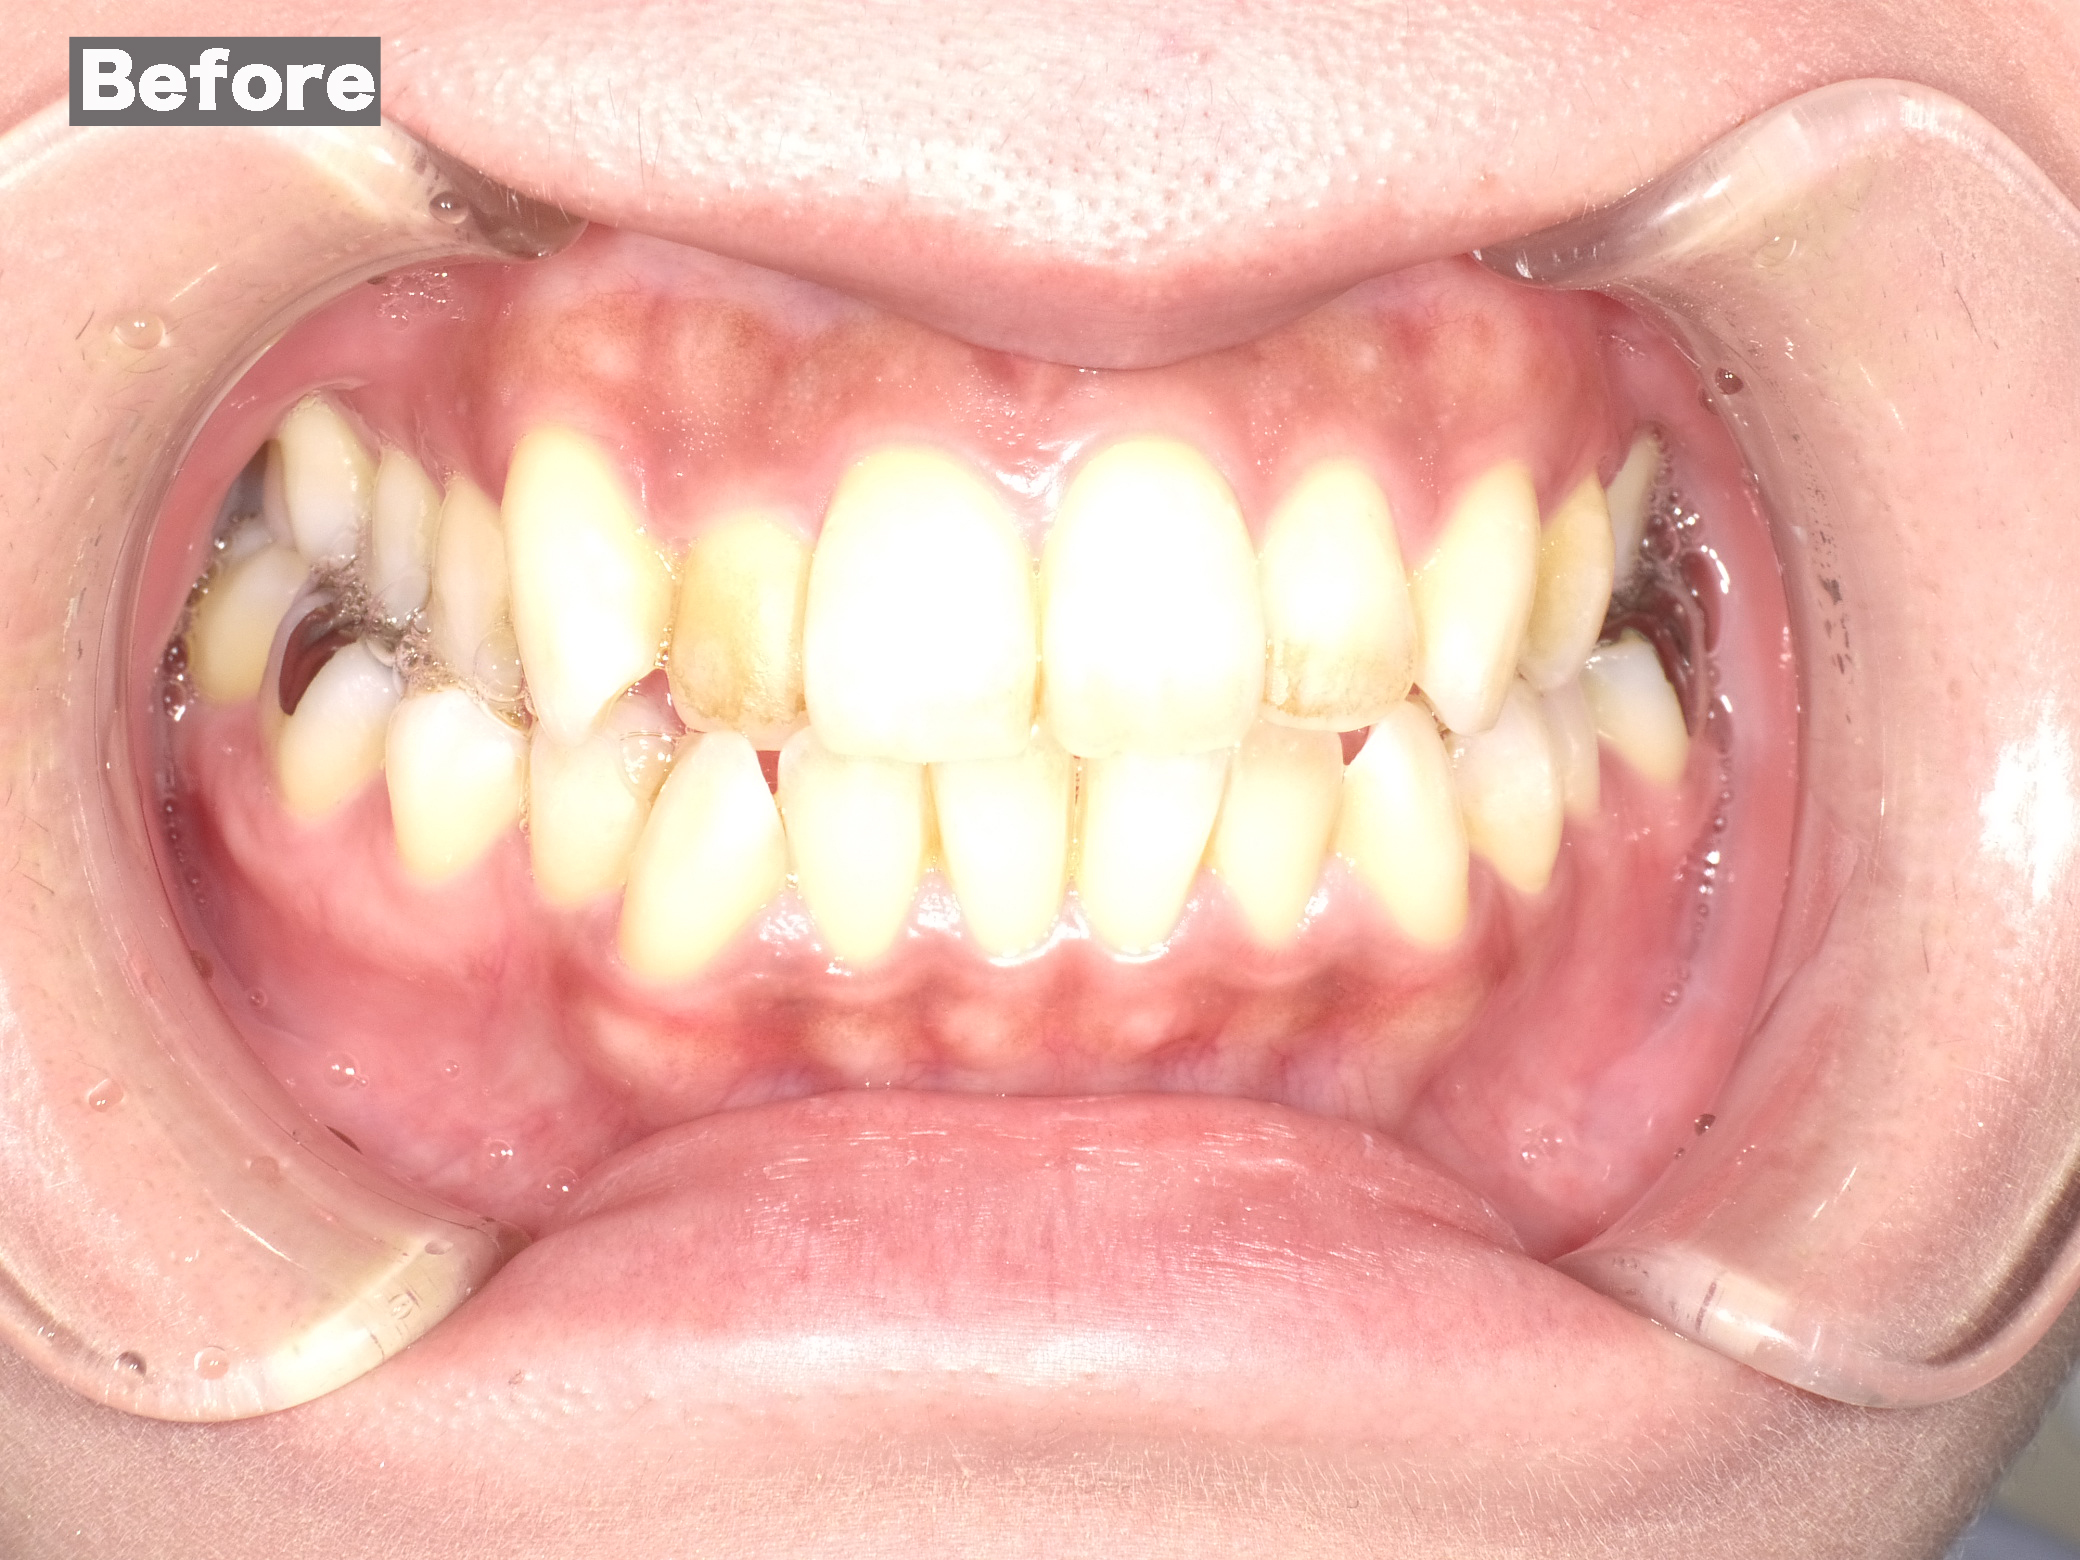

ワイヤー矯正

Case006 – ワイヤー矯正

片顎抜歯を行い、主に上の前歯の歯並びを矯正した症例です。

Case005 – ワイヤー矯正

Case004 – ワイヤー矯正

上下左右4本の抜歯を行い、全体の歯並びを矯正した症例です。

Case003 – ワイヤー矯正

Case002 – ワイヤー矯正

下の歯が前に出てしまう、いわゆる「受け口」を矯正した症例です。

Case001 – ワイヤー矯正